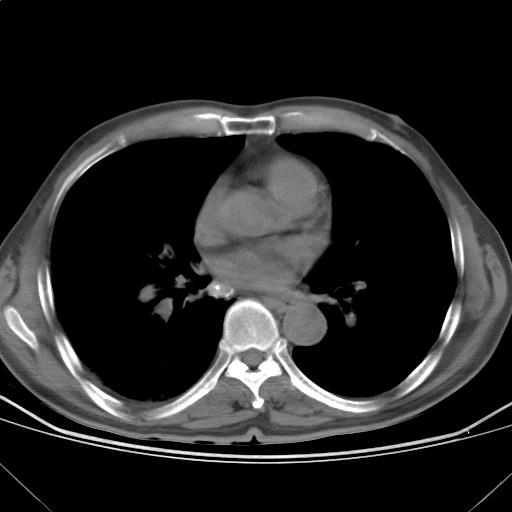

以下是引用随光逐影在2009-5-1 13:53:00的发言:[br]考虑为:1)两肺血行播散型肺结核;2)右肺下叶炎症感染。3)右侧胸膜增厚。